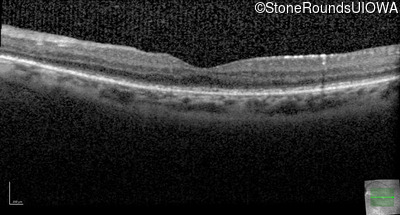

Optical Coherence Tomography - Left - 20/50 +1

Exemplar / OCT Stack